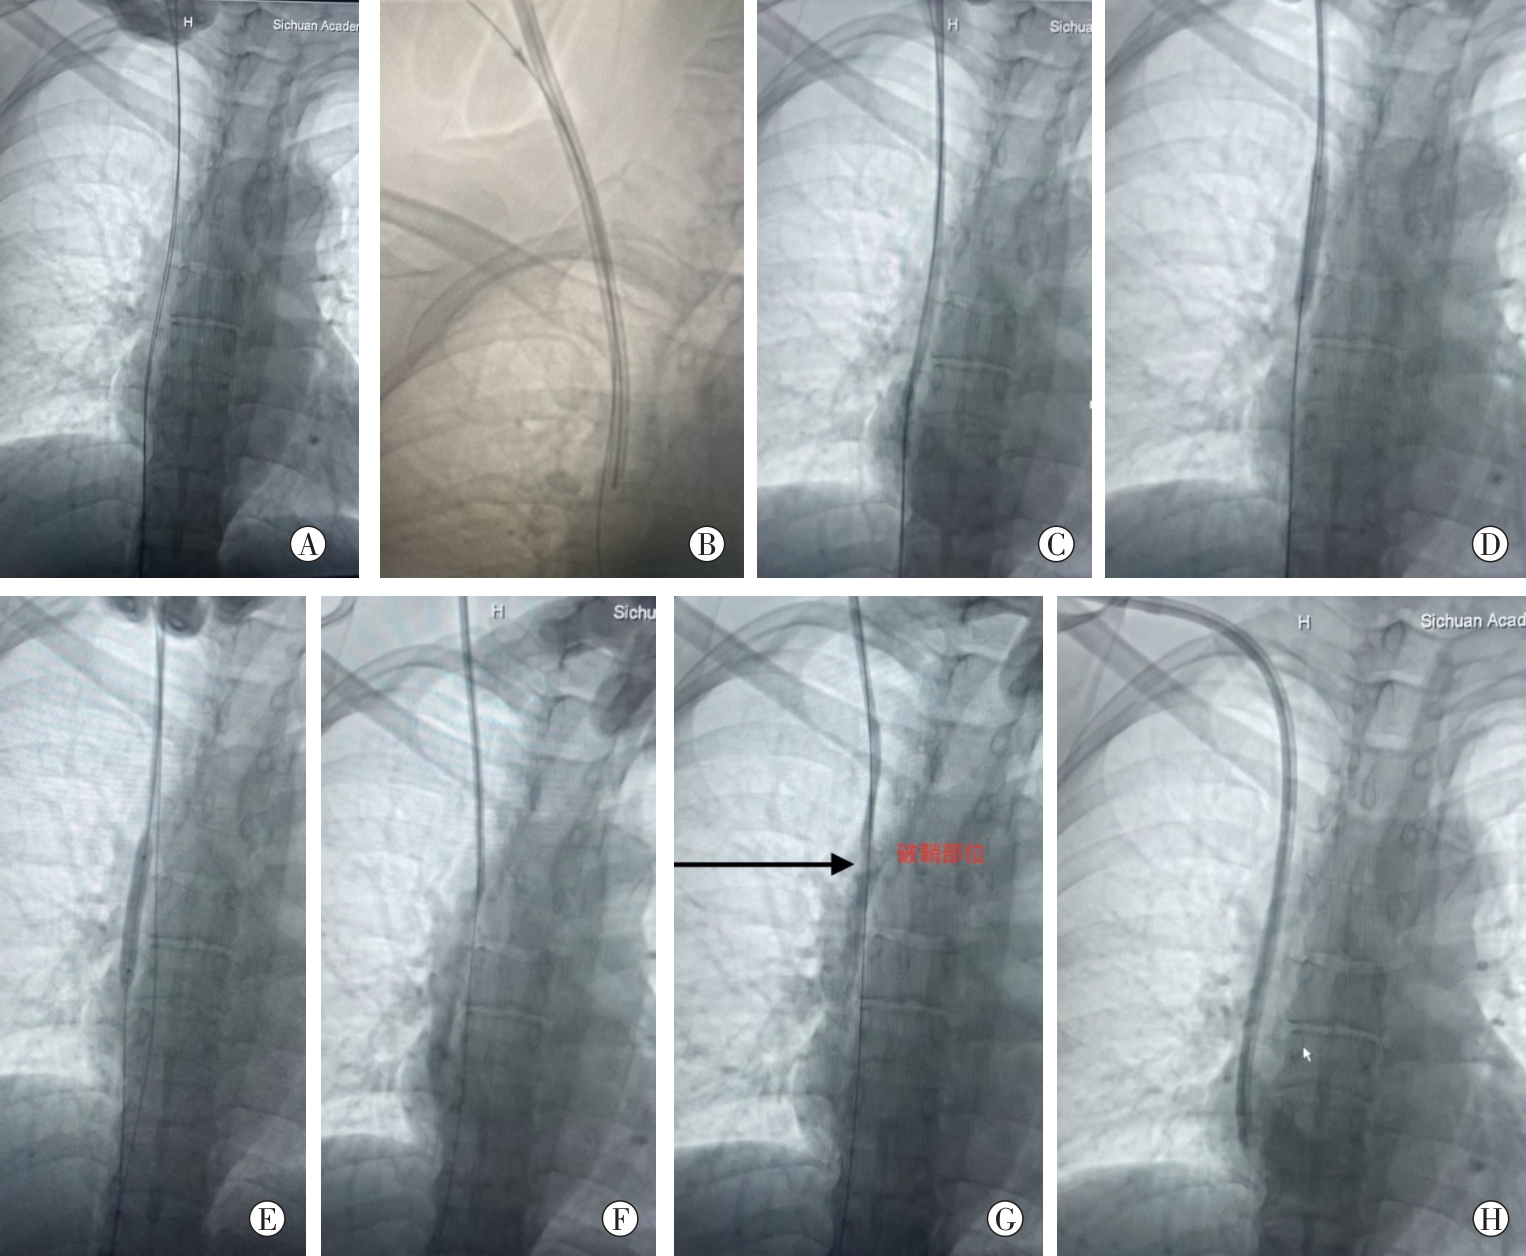

图1

双导丝联合球囊导管破鞘手术步骤

注:

A:保留双导丝在血管内,拔除导管;B:在纤维蛋白鞘内、导管壁外之间的间隙放置导丝;C:沿导丝A置入血管鞘;D:球囊沿导丝A全程扩张纤维蛋白鞘;E:球囊阻塞纤维蛋白鞘下段,导丝V退至球囊上方突破纤维蛋白鞘;F:退出导丝A及血管鞘,沿导丝V重新放置血管鞘;G:球囊沿导丝V扩张破鞘部位的纤维蛋白鞘,破鞘后上腔静脉充分显影;H:沿导丝V顺利更换导管